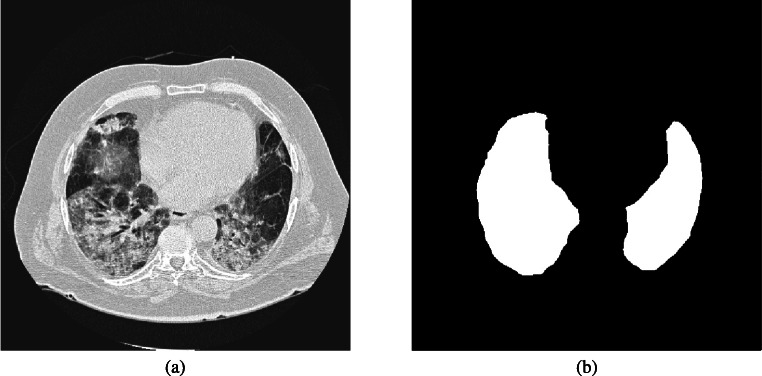

Fig. 1.

A thoracic CT image (a) with its segmented lung mask (b). The uneven grayscale distribution of the image caused by pathological abnormities makes lung segmentation a difficult task